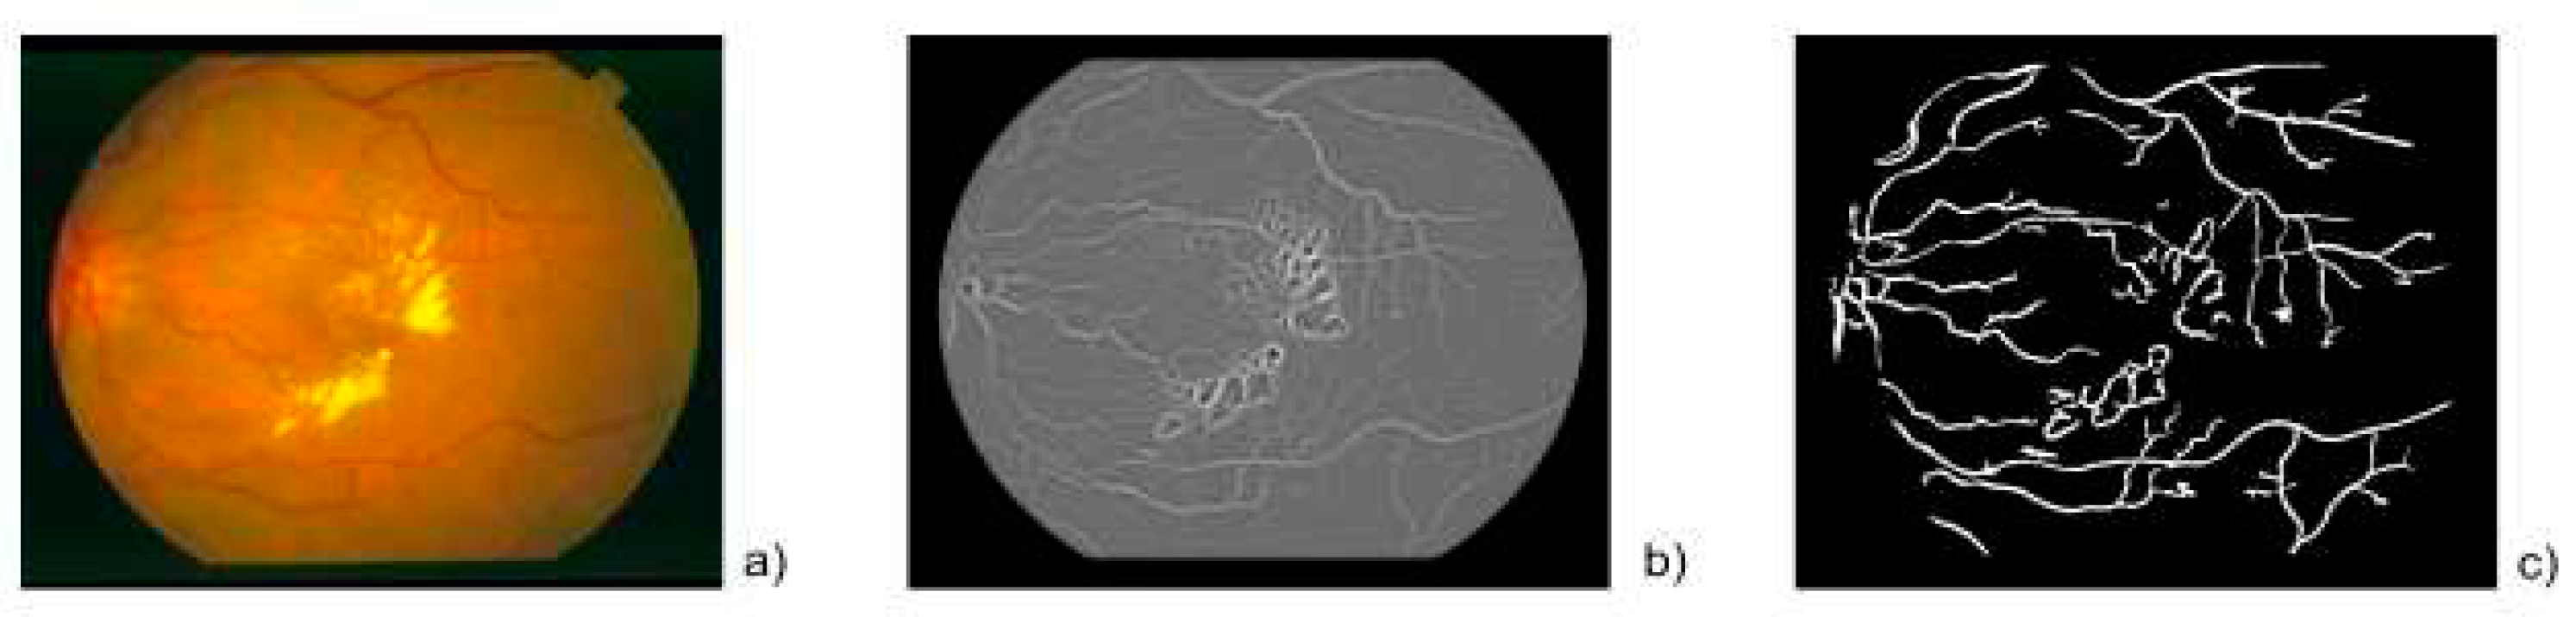

Fractal Analysis of nets microvasculars in human retinas (23).

- Santiago-Cortes, E., J. L. Martınes-Ledesma, and D. A. Mantilla. “Análisis fractal de redes microvasculares en retinas humanas.” Journal de Ciencia e Ingeniería 12.1 (2020): 230-242.

- Hoover, A.; Kouznetsova, V.; Goldbaum, M. Locating blood vessels in retinal images by piecewise threshold probing of a matched filter response. IEEE Trans. Med Imaging 2000, 19, 203–210. [Google Scholar] [CrossRef] [PubMed]

- E. Santiago-Cortés and J. M. Ledezma, “Dimensión fractal en retinas humanas,” Journal de Ciencia en Ingeniería, (2016), vol. 8, no. 1, pp. 59–65.